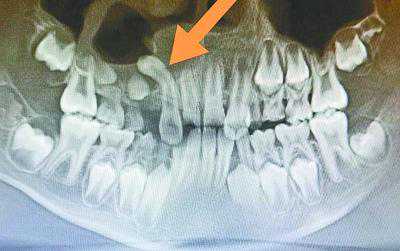

“翻跟头”的多生牙。

经多方打听,洋洋的妈妈李女士找到了省妇幼保健院口腔科副主任医师吴茜主任求诊。8月21日,吴茜面诊之后,先让洋洋拍了一个口腔CT定位多生牙,发现腭侧多生牙位于上颌窦底,与上颌窦穿通,并呈180度倒置反转。而且,这颗多生牙还“鸠占鹊巢”,挤占了右上尖牙的位置,导致右上尖牙牙胚高位阻生。